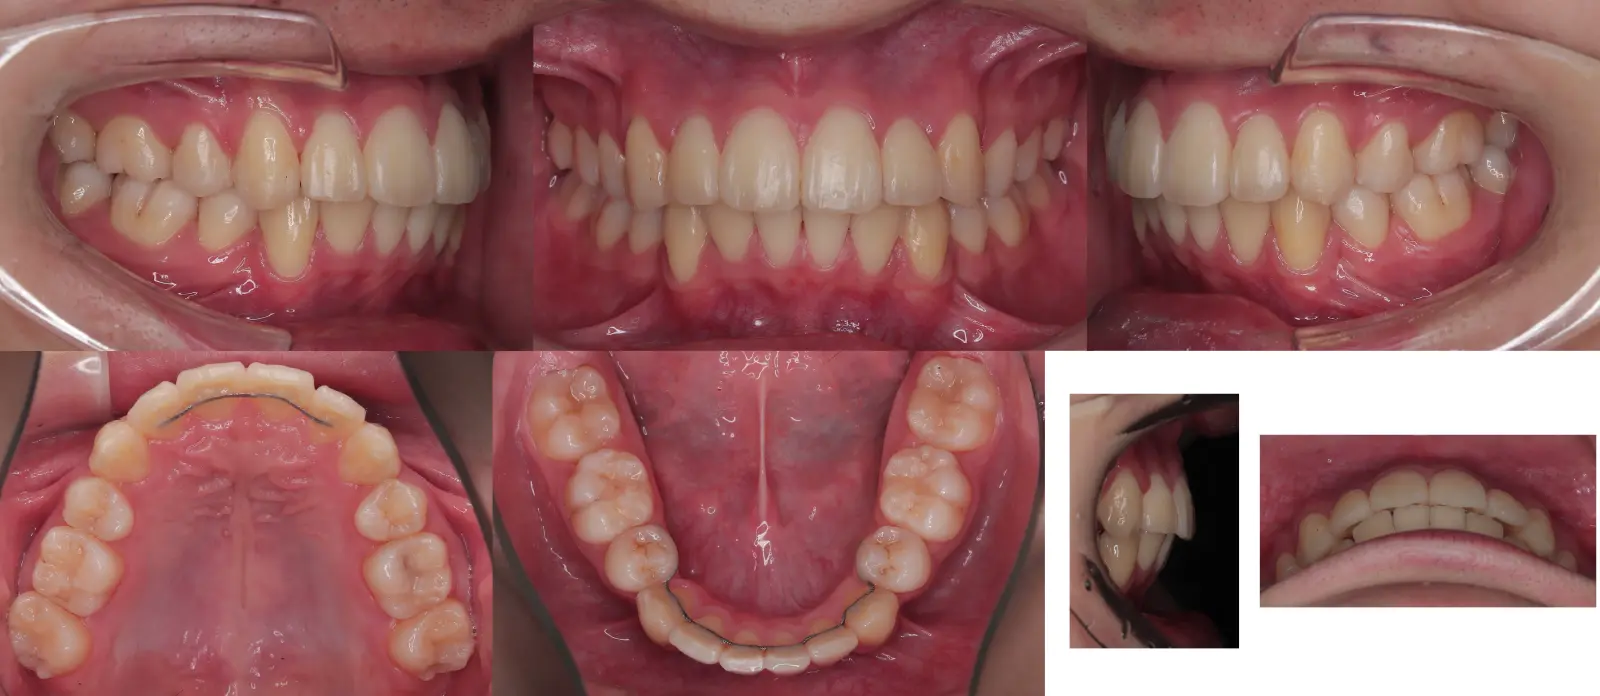

非対称を伴う叢生

- 主訴

八重歯

- 年齢

10代

- 治療期間

2年6ヶ月

- 治療回数

24回

- 治療に用いた主な装置

カスタムメイド型リンガルブラケット矯正装置(WIN)

歯科矯正用アンカースクリュー

- 治療費

1,200,000円(税別)トータル料金

- 抜歯部位

上下顎第一小臼歯4本